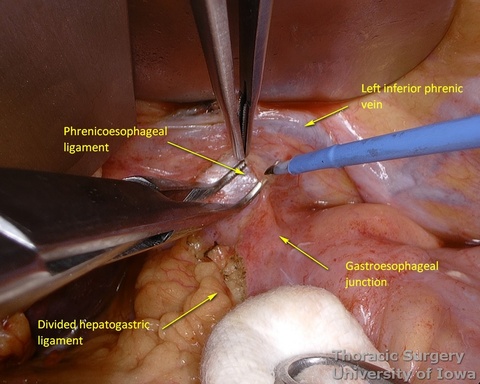

- The pars flaccida is incised and the gastrohepatic ligament is completely opened towards the esophageal hiatus.

- Phrenoeosophagial ligament is formed by the transversalis fascia of abdomen and endothoracic fascia and is covered with the peritoneum. Thicker upper leaflet ascends obliquely and fuses with the adventitia of the esophagus above the diaphragm. The thinner lower leaflet runs caudally and attaches to the esophageal wall just cranial to the angle of His. The triangular space between the leaflets is filled with the perihiatal fat pad.

- The peritoneum is incised around the hiatus.

- The phrenoesophageal ligament is divided and the right crus dissected.

- Subhiatal fat ring is exposed after division of the lower leaflet of the phrenoesophageal ligament

- The abdominal esophagus, periesophageal fat, and nodes are dissected and encircled with a Penrose drain for retraction.